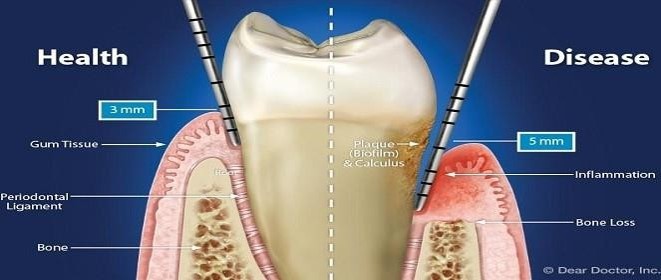

Kesehatan pada gigi geligi juga sangat dipengaruhi oleh kesehatan jaringan periodontal. Kondisi jaringan periodontal sehat adalah suatu kondisi gusi dan tulang yang sehat, tidak ada pendarahan, tidak ada karang gigi pada gusi, dan tidak adapenurunan sulcus gingiva atau poket.

Jaring periodontal atau jaringan penyangga gigi terdiri dari:

- Gingiva / gusi

- Ligament periodontal

- Tulang alveolar

- Sementum

Penyebabnya infeksi jaringan peridontal, diantaranya oleh karena penumpukan plak dan bakteri yang lama kelamaan akan berakumulasi menjadi kalkulus/ karang gigi, infeksi yang disebabkan oleh gigi berlubang, akibat dari konsumsi obat – obatan, dan penyakit bawaan seperti diabetes militus.

Infeksi gusi yang merusak jaringan lunak dan tulang penyangga gigi disebut periodontitis. Jika infeksinya tidak diobati, lambat laun akan menyebabkan terbentuknya celah atau kantong pada gusi yang memisahkan antara jaringan gusi dengan gigi sehingga menyebabkan gigi goyang dan infeksi gusi.